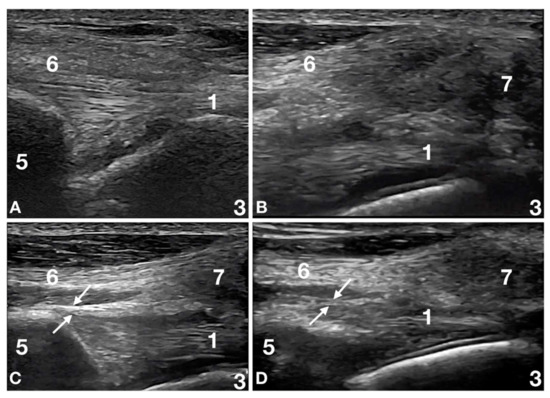

2.3. Ultrasound Evaluation